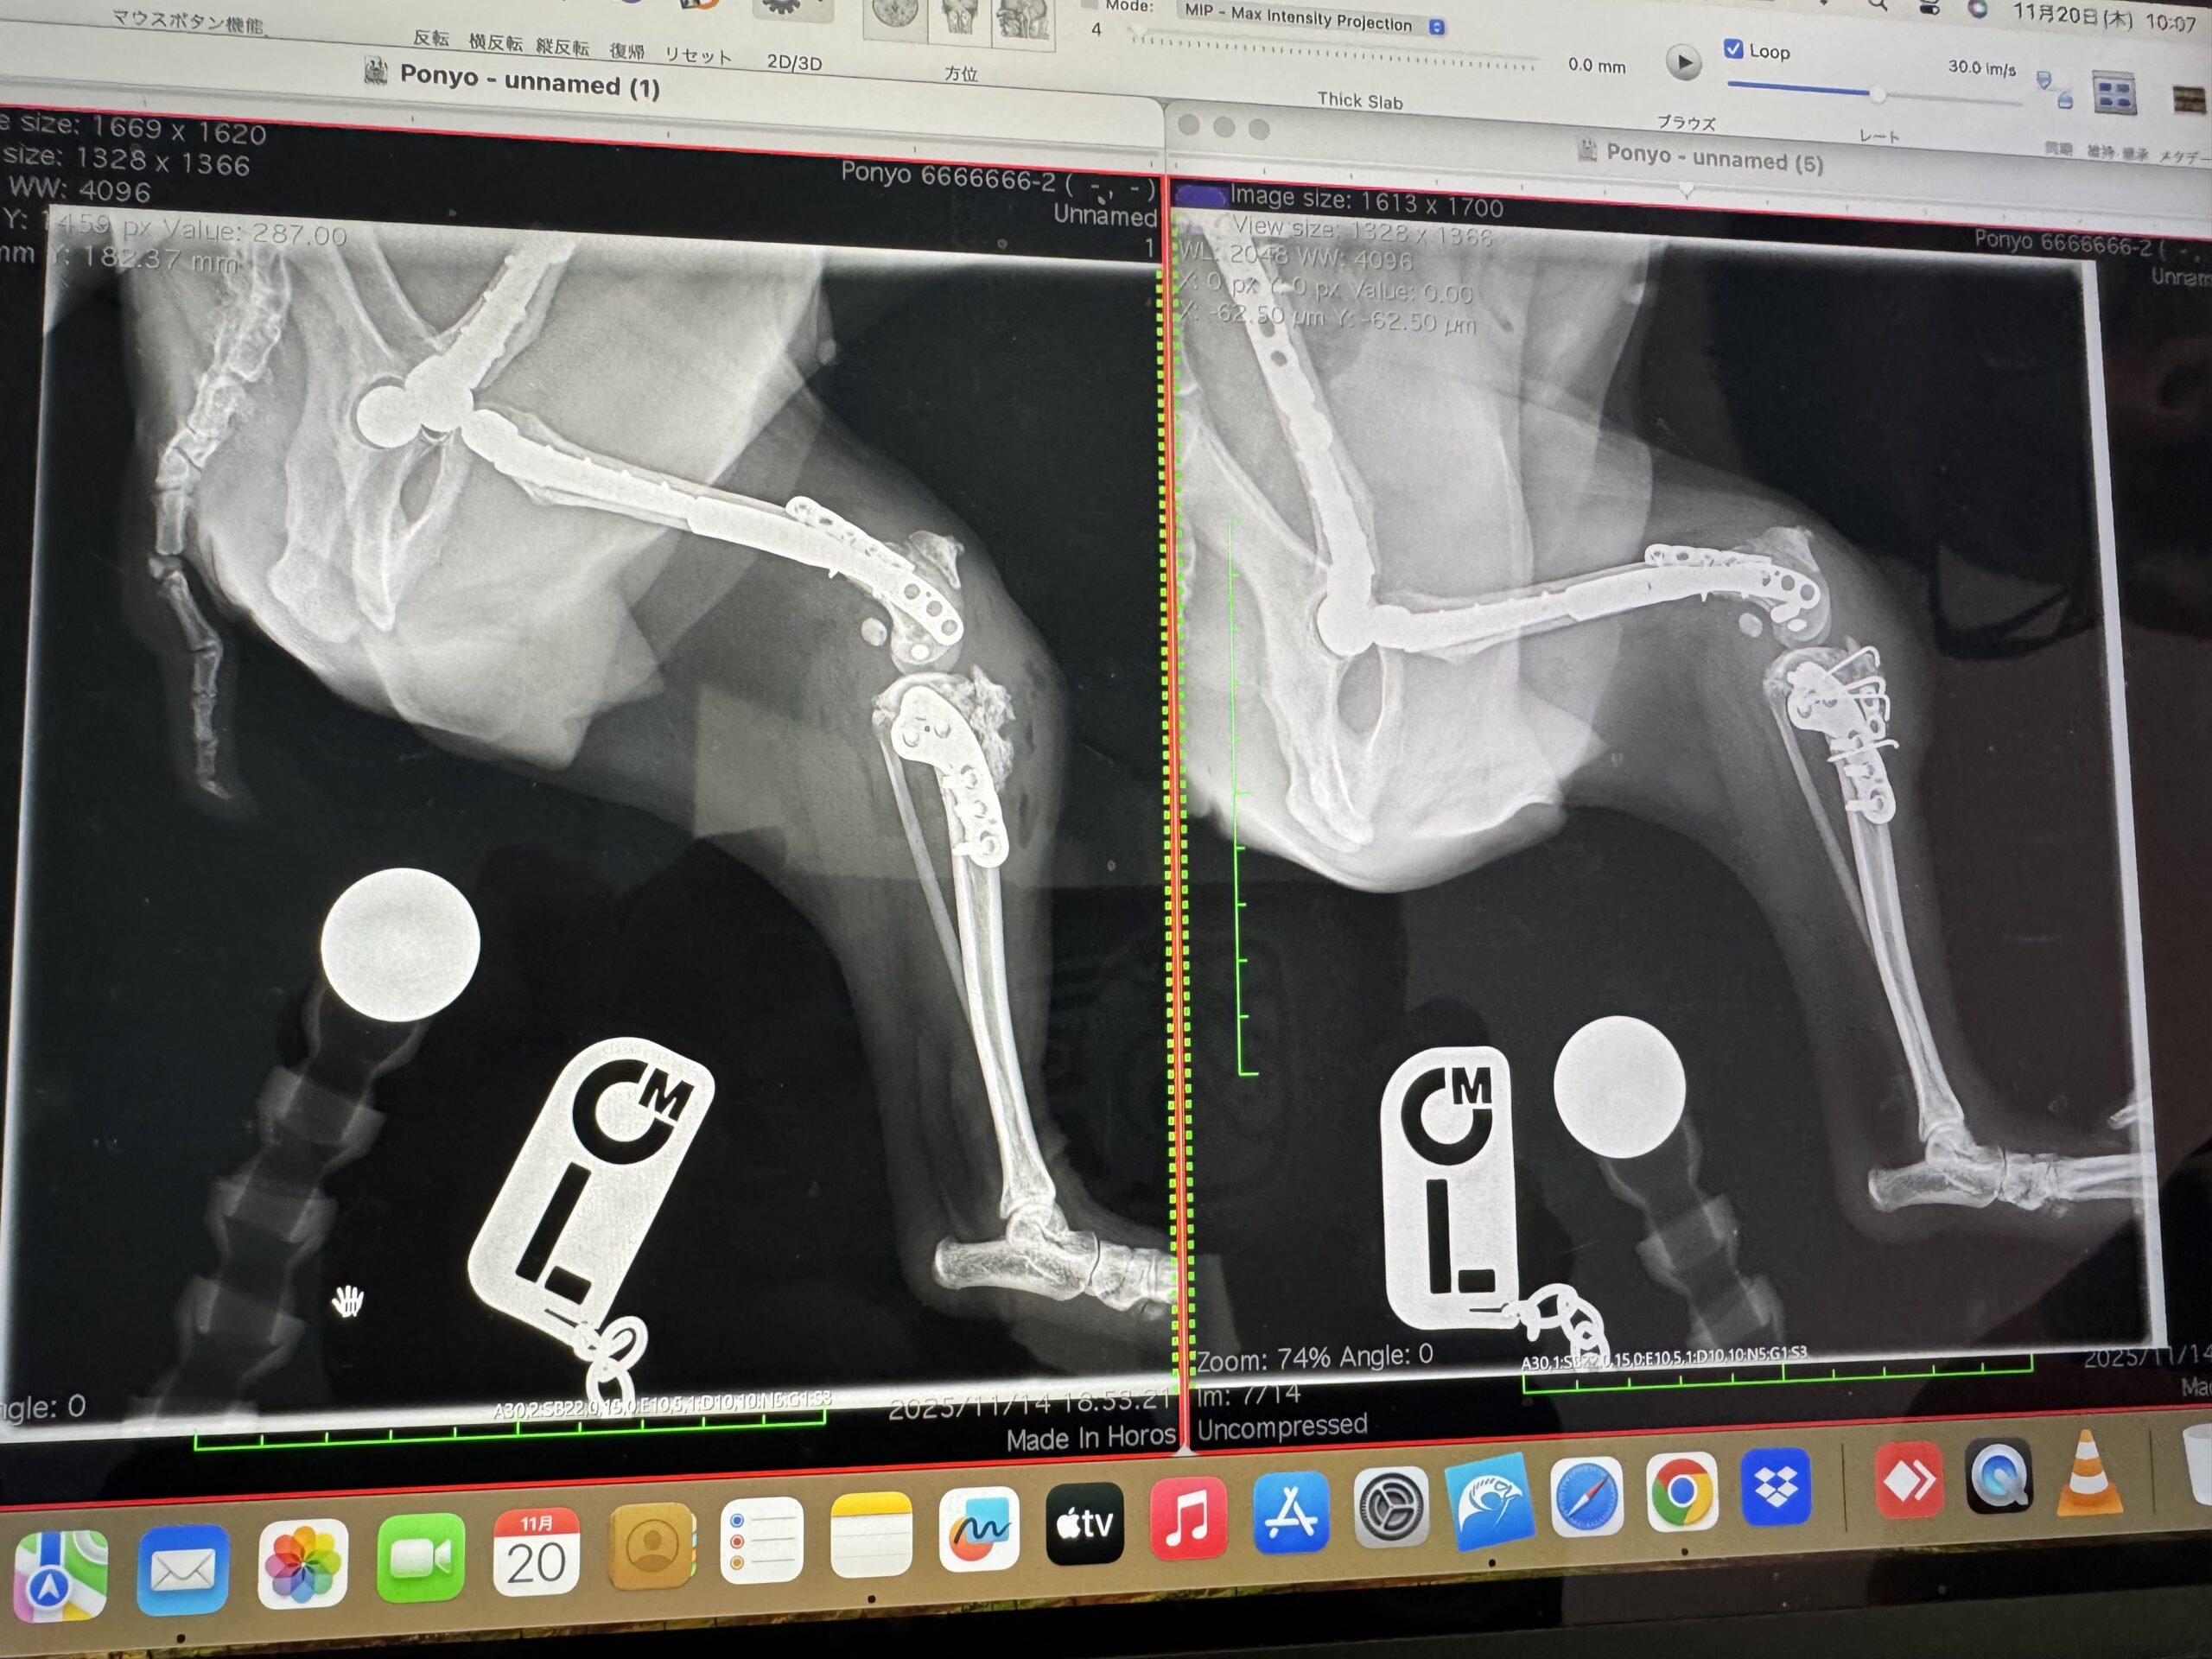

11月11日に日帰りの予定で受診をしましたが、薬の量を多くすることで、浸出液も止まり、状況が改善しているはずだった後ろ足の状況がほぼ変わっておらず、その場で術式変更となりました。

予定より多くの人工物を抜く方針になり、手術日が変更となりそのまま入院となりました。

手術内容

・抜釘手術(両膝)

無事に手術が終った連絡を受けましたが、さらなる試練が。

入院時から前足の足首が私でも言われれば分かるほど急速に変形しており、免疫疾患がかなりのスピードで進行をしている状況でした。

(左が術後、右が術前)